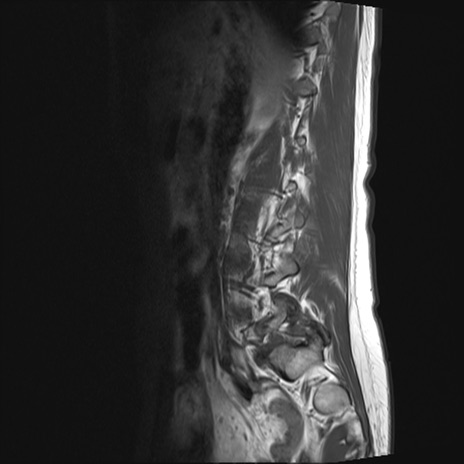

腰椎MRI

横断像と矢状断像